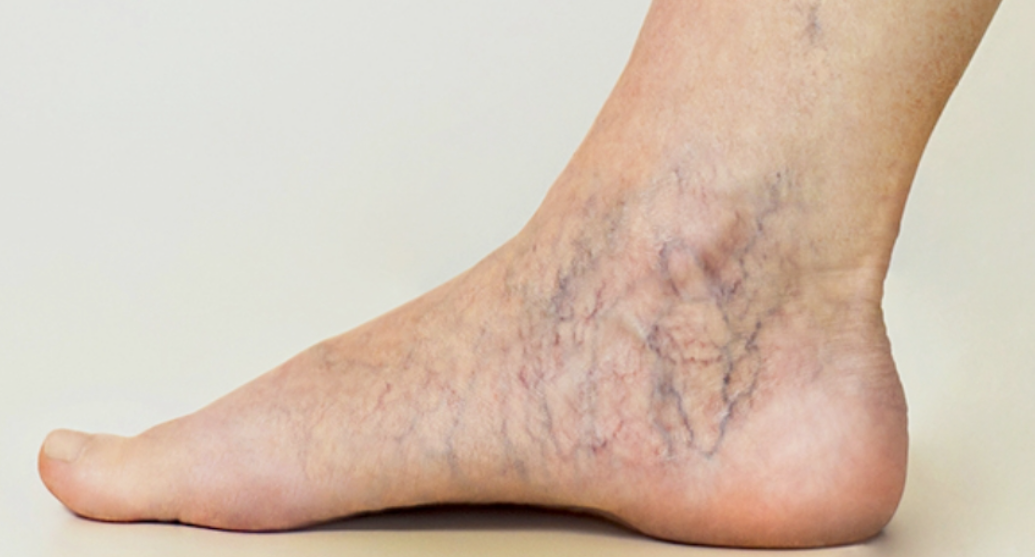

하지정맥류는 다리의 정맥이 확장되고 비정상적으로 늘어나면서 발생하는 질환입니다. 정맥이 비정상적으로 늘어나는 이유는 주로 혈액이 원활하게 흐르지 못하고 정체되기 때문입니다. 이러한 현상은 특히 오랜 시간 서 있는 자세를 유지하는 사람들에게 흔히 발생합니다. 하지정맥류의 주요 증상으로는 다리의 통증, 피로감, 부종, 그리고 피부 색소 변화 등이 있습니다.

이 질환은 단순한 미용상의 문제가 아닙니다. 초기 단계에서 적절한 관리가 이루어지지 않으면 심각한 합병증으로 발전할 수 있습니다. 예를 들어, 혈전 형성과 같은 혈관 질환이 발생할 수 있으며, 이는 생명을 위협할 수도 있습니다. 그러므로, 하지정맥류에 대한 이해와 예방은 필수적입니다.